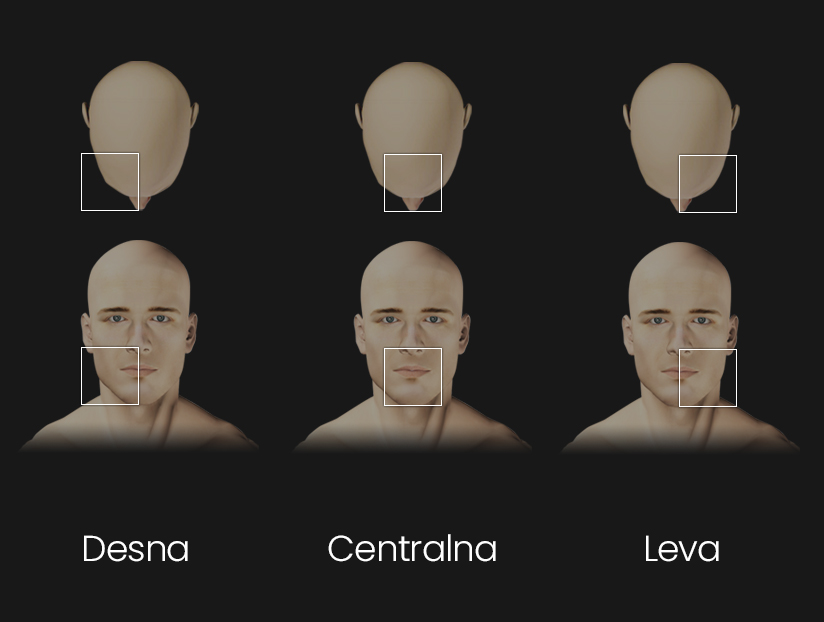

Izaberite jednu od 3 zone za snimanje i planiranje terapije

Precizni snimak 8×8 cm određene strane gornje i donje vilice koji obuhvata sve zube gornje i donje vilice u zoni snimanja. Centralna zona od 5 do 5 obe vilice, Leva zona od 4 do umnjaka obe vilice – levo, Desna zona od 4 do umnjaka obe vilice – desno.